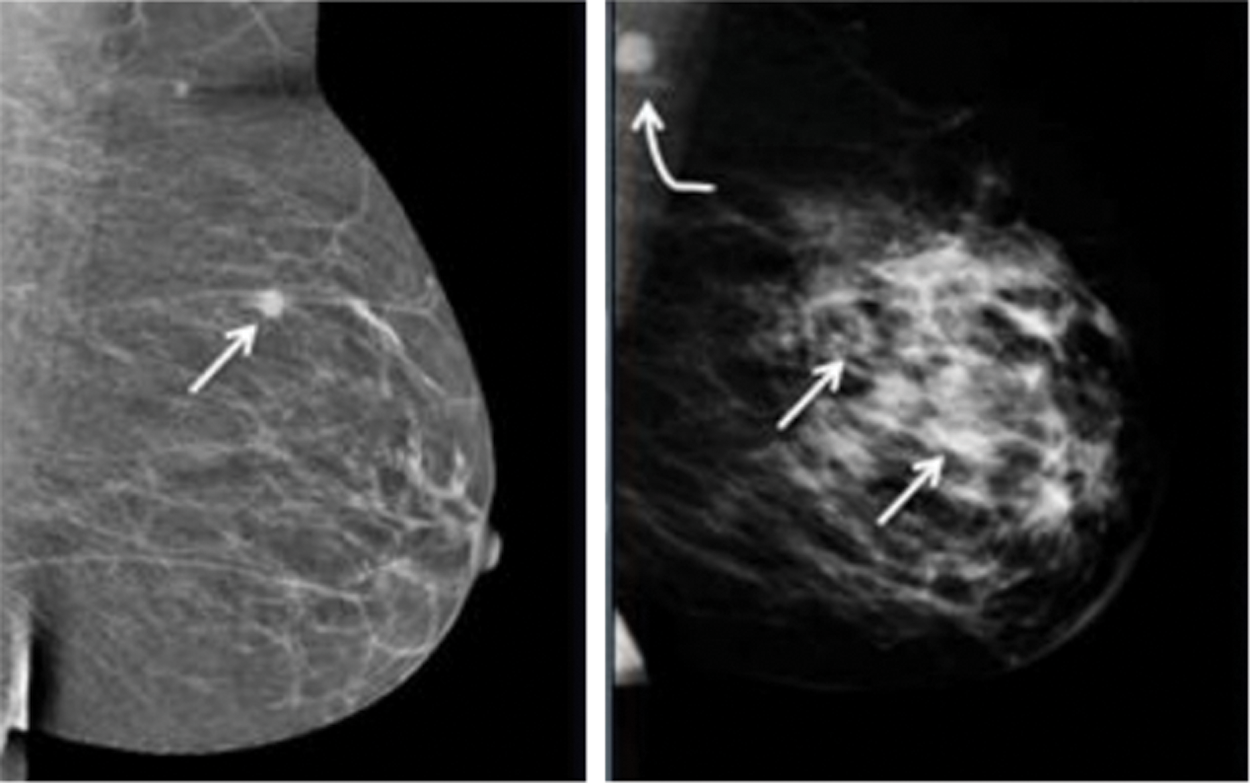

Breast cancer is a widespread disease among women, with a significant increase in its mortality rate. A survey in 2012 found that around 25.2% of women globally were directly affected by breast cancer. An earlier study by the American Cancer Society stated that around 246,660 females and 2,600 males would be identified with persistent breast cancer in 2016 [1]. The study was proved correct, and the number of patients has been increasing rapidly. Therefore, to increase human lifespans, the disease must be predicted at an earlier stage, which would increase the survival rate by up to 90% [2]. Regular monitoring and primary detection are necessary to avoid further adverse developments in breast cancer. There are various methods to detect cancer, including mammography, ultrasound, X-ray, and positron emission tomography (PET). X-ray mammography utilizes lower amounts of X-ray energy to create the pixels of the disease. These images are helpful in early diagnosis. Many reviews have underscored the threat of exposure to radiation [3,4]. Mostly, women at the age of 40 years are observed to face more difficulty during ordinary mammography screening procedures than elderly women. A study on mammogram results stated that 1,212 of 10,000 women showed false positives for breast cancer at the age of 40 years. The injurious impacts of mammography include overtreatment, unwanted and persistent follow-up testing, and stress related to false-positive test results. Moreover, X-ray mammography necessitates the encoding of the breast as it lies flat during the examination process, which causes pain. Distinguishing tumors from mammogram images is a complex process [1–4] because of the similar appearances of the cancer and the massive cell growths that appear white in color in the mammogram pixels and the fatty cells that are black in color. In Fig. 1, tiny cancer cells are noticeable in the fatty breast; At the same time, the formed breast tissue in the heterogeneous large breasts has a possible 4 cm tumor.

Figure 1: Sample breast cancer image